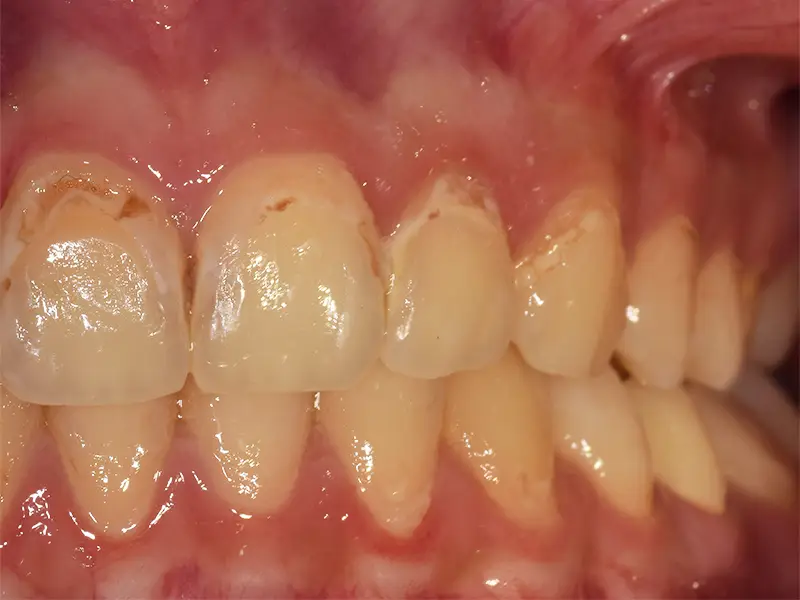

L’odontoiatria conservativa ha l’obiettivo di curare i denti colpiti da carie o lesioni senza ricorrere all’estrazione, ripristinando forma, funzione ed estetica. È un approccio moderno, poco invasivo e focalizzato sulla preservazione del tessuto dentale sano.

- In presenza di carie di qualsiasi entità

- Per riparare scheggiature o fratture dentali

- Per sostituire vecchie otturazioni danneggiate

- In caso di erosioni o abrasioni da spazzolamento